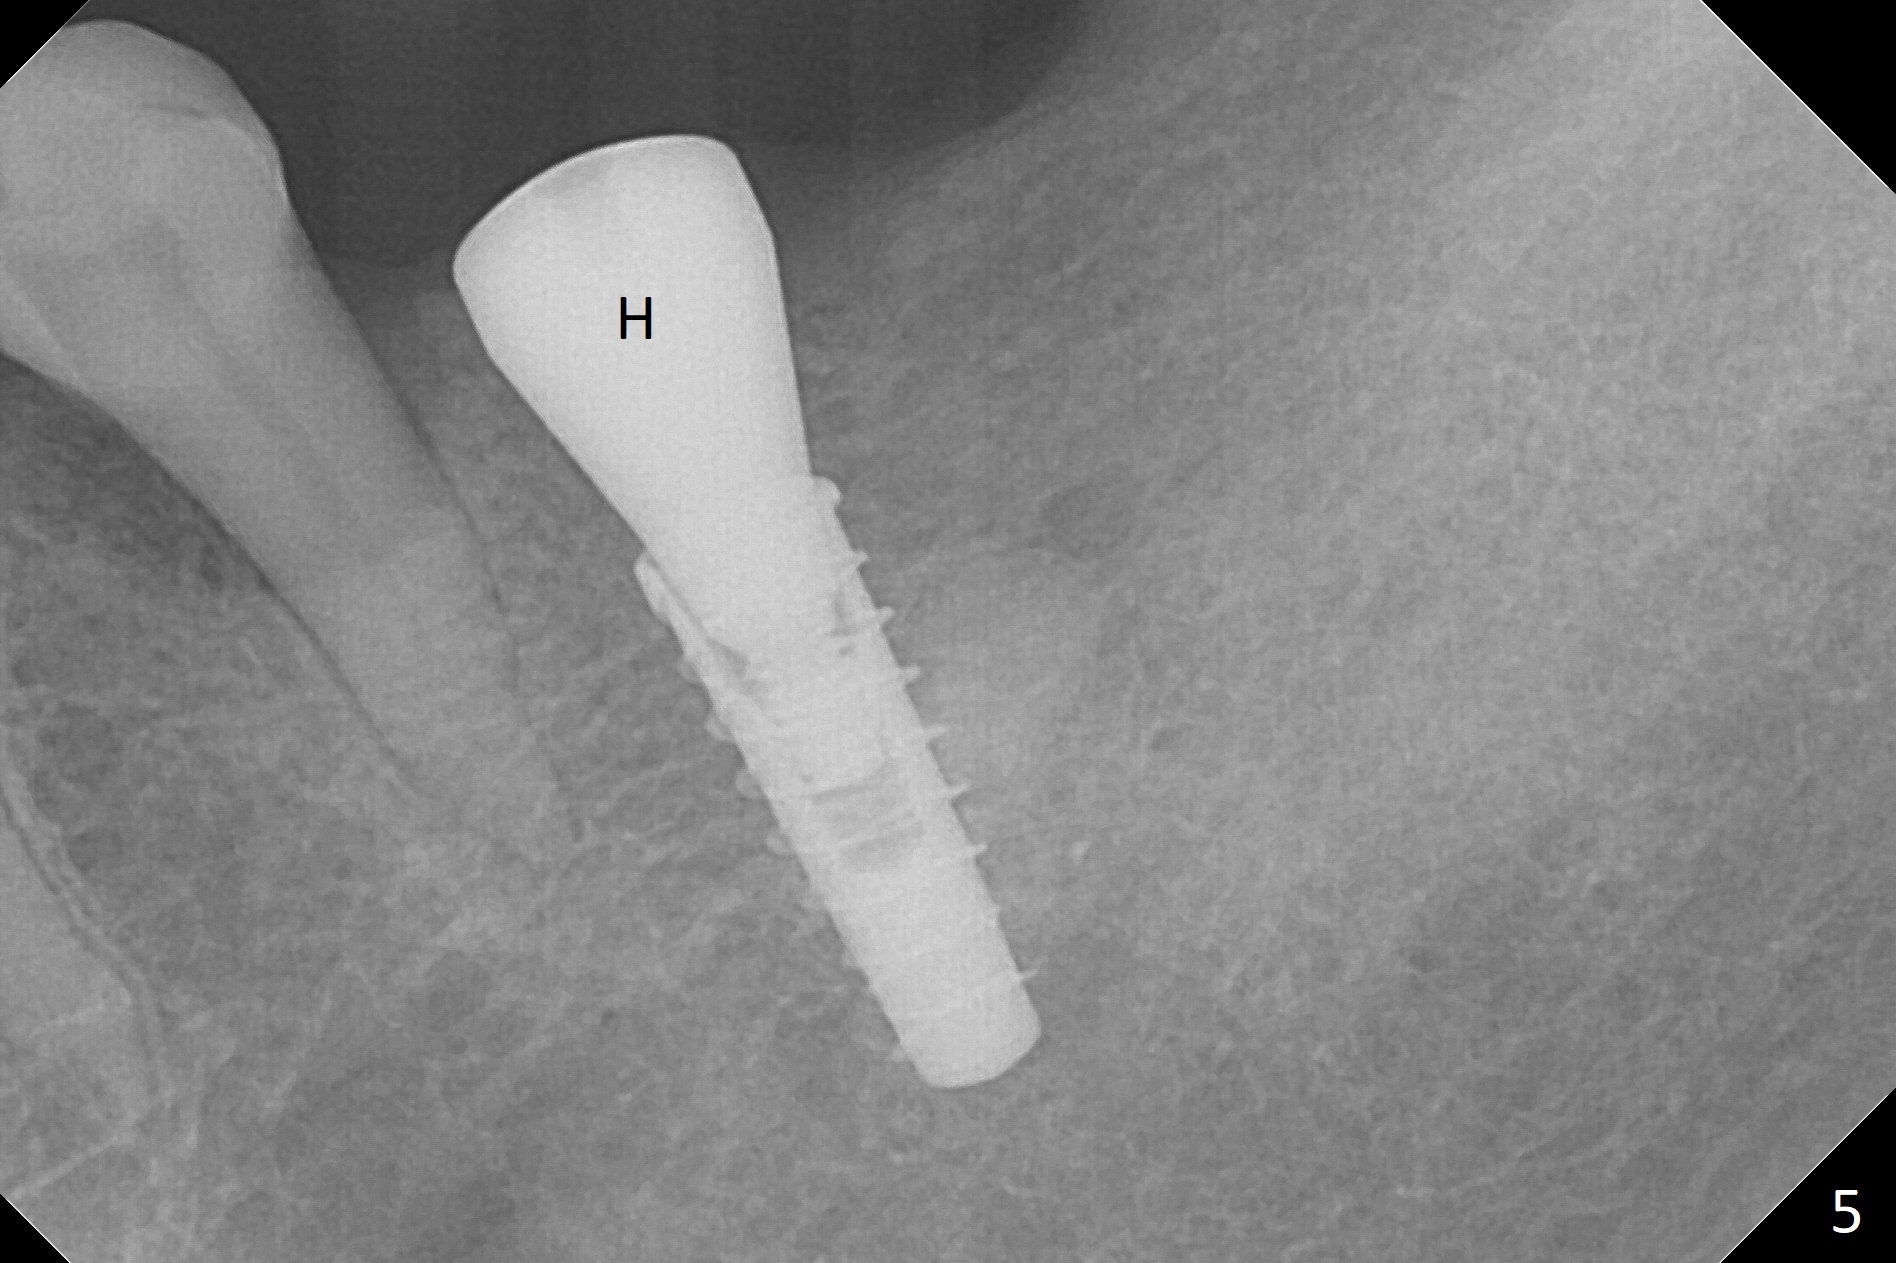

After incision over the narrow ridge at #30 (Fig.1) and ridge reduction (Fig.2 black area on the top; Fig.4 arrowheads), a 1.6 mm drill is used (Fig.2 (CBCT coronal section) long vertical black area) to start BEB (bone expansion and Bending). It is expected that the cortical and cancellous bone of the buccal (B) and lingual (L) plates can be expanded after use of Magic Expanders (ME) and 1.6 mm drill alternatively. In fact it appears that only the cancellous bone is pushed after MEs from 3 to 4.3 mm (Fig.3 arrows). There is no apparent cortical bone bending. There may be cancellous bone condensation. Dummy (Fig.4) and definitive (Fig.5) implants (4x11 mm) are placed. Since torque is 20 Ncm, a 5.5x4 mm healing abutment is placed (Fig.5,6 H). The opposing tooth is supraerupted; intrusion is pending. A 6x4(2) mm abutment is placed with a provisional 2 months postop. There is enough occlusal clearance. Impression is taken 5 months postop with difficulty because of subgingival margin (Fig.7). After cementation, the patient feels discomofort, which is relieved when the mesial embrasure is enlarged. Return to Lower Molar Immediate Implant, Armaments Xin Wei, DDS, PhD, MS 1st edition 12/14/2017, last revision 09/16/2018